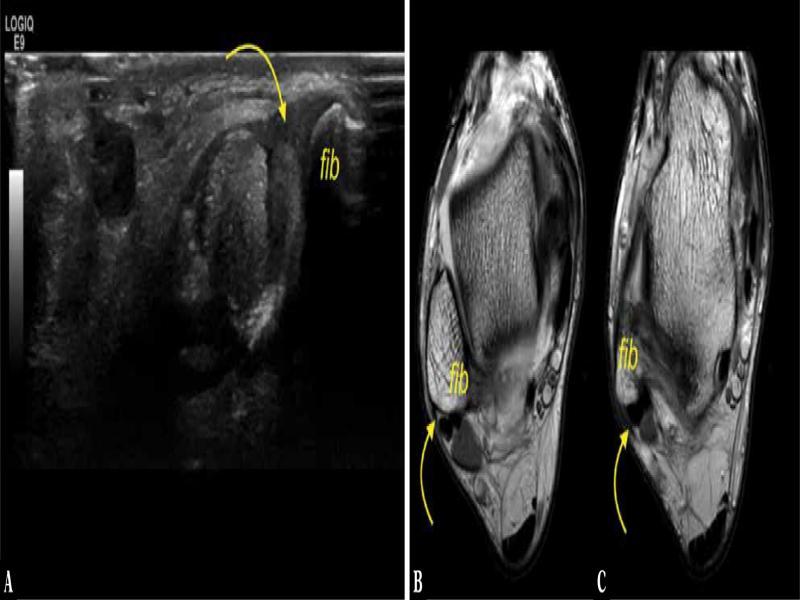

Fig. 1.

A 19-year-old patient with a clinical suspicion of rheumatoid arthritis. A. ultrasound, transverse section. B, C. proton density-weighted transverse sections. Fib – fibula. SPR – curved arrow. No connection with IER is present